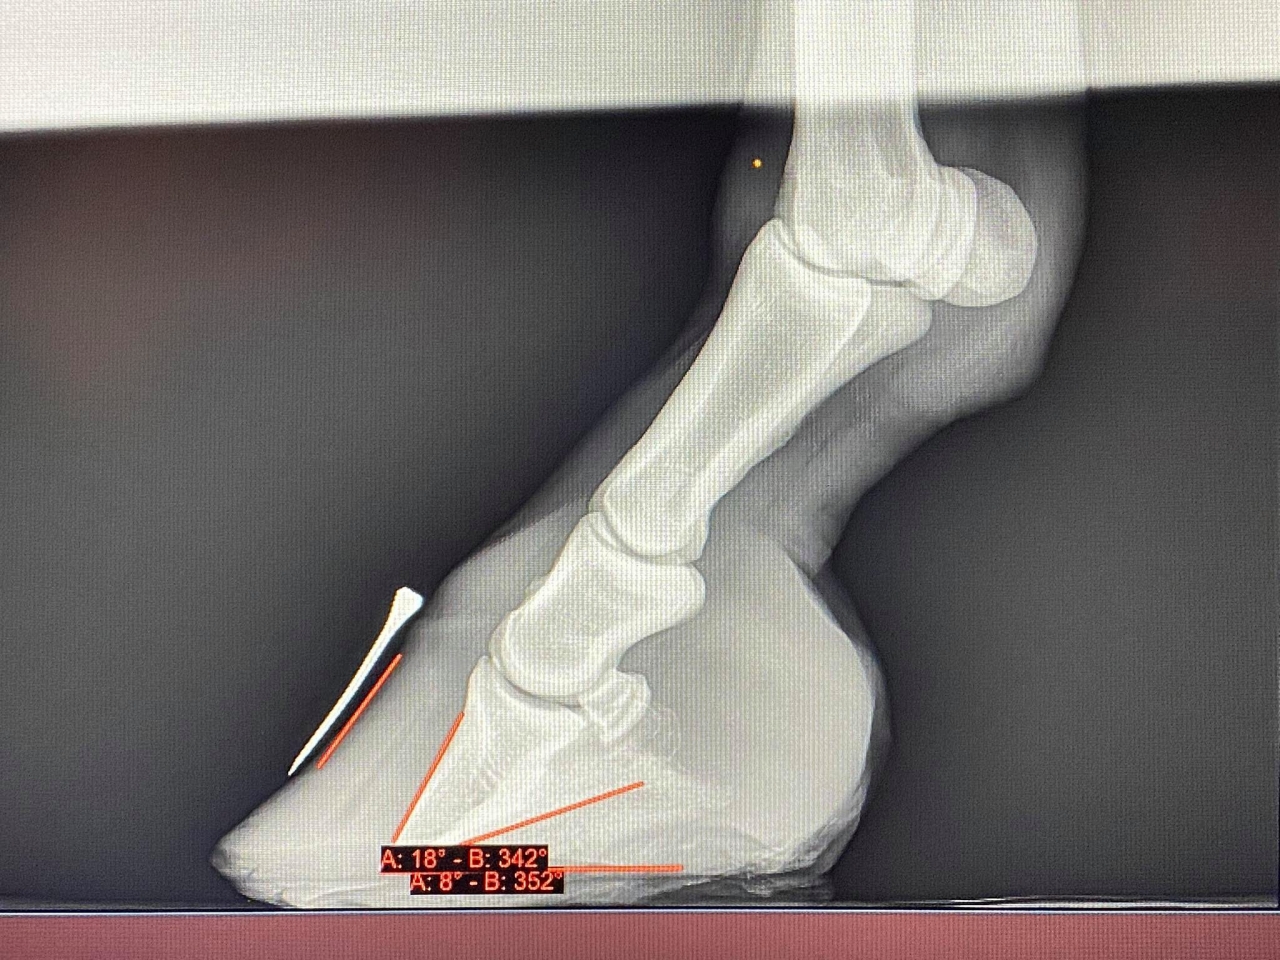

DéconnectéDire merci | muesli08 Au sujet des radios, oui je les ai vues. Est ce que vous pourriez poster toutes les radios et peut être obtenir de votre vétérinaire les radios sans notation écrite dessus car elles masquent une partie des radios, en particulier elles empêchent de voir clairement l'épaisseur de la sole? Certainement qu'en discutant avec Remco, il vous a précisé les points importants du parage de réalignement, dont le fait, dès le premier parage de raccourcir la pince de façon à ramener le point de bascule à sa vraie position c'est à dire juste devant la vraie ligne blanche ( pour corriger l'angle dorsal ) et de faire un chanfrein en pince et sur tout le pourtour du pied ( pour supprimer les forces de séparation exercées sur les lamelles affaiblies/la paroi du sabot par le poids du cheval et permettre à la nouvelle paroi qui pousse à partir de la bande coronaire de pousser dans le bon angle parallèle à la face dorsale de P3). Les talons doivent être abaissés pour restaurer un angle palmaire autour de 5 degrés. Je ne vois pas bien à cause des inscriptions sur la radio mais la sole ne semble pas très épaisse sous la pointe de P3; il est important que la sole se développe à cet endroit et donc les talons doivent être abaissés qu'à partir de la hauteur de la fourchette, ce qui va laisser le pied en 2 plans au niveau de sa surface solaire, le temps que la sole se développe à l'avant du pied mais ce n'est pas grave si les piesds sont bien soutenus dans des boots avec des semelles épaisses à l'intérieur. J'essaie de vous faire des tracés sur les radios pour que cela soit plus clair si vous le souhaitez et de vous envoyer des infographies sur le sujet. |

| Dire merci | ![]() voilà j'ai réussi et oui j'ai lu sur la page TLS Elle a déjà eu un premier parage avant radio où les talons ont été baissé une bonne fois (je pense qu'il avait retiré plus d'1/2 cm, les talons étaient à 25mmm, depuis je l'ai descendue à 20mm jusqu'au plan de la sole, avec chanfrein et la pince avait bien été reprise également pour retirer la pression lamellaire, c'est d'ailleurs après ce premier parage à J11 qu'elle s'est sentie beaucoup mieux ! |

| Dire merci | bon je viens donner des nouvelles ! radios de mercredi : ![]() ![]() la rotation es déjà bien corrigée là il me reste à rétablir un point de break over parfait : surtout sur base de la punaise à l'apex qui me permettra de couper pile poil où il faut. ça repousse , lentement ne pince, plus vite en talons ce qui donne de précieuses indications : que je dois surveiller la hauteur de talons chaque semaine et les garder à hauteur de la sole en permanence. Muesli n'est plus du tout sensible sur sol souple !!! Elle garde tout de même ses chaussures et semelles en permanence : vu la poche de gaz , je dois me méfier , la laisser marcher sans soutien pourrait accentuer la bascule. je pare les prochains jours (j'attends les mark ups, j'ai bien ma petite idée, mais je ne peux me permettre d'être approximative. ) édit car j'oublie toujours de refermer les parenthèses que j'ouvre et aussi pour vous dire : regardez comme la sole s'est épaissie sous la pointe de p3 en 3 semaines !! Message édité le 06/12/20 à 19:33 |

En ligneDire merci | la sold a bien repris c’est top et la deuxième radio l’alignement est pas mal du tout tu as vraiment de quoi reprendre en talon et en pince en plus. les poches de gaz vont partir avec la reprise en pince sur tes parages c’est douloureux donc fais gaffe à bien garder le pied dans des boots . maintenant c’est surtout le pied de la première radio à travailler pour reprendre l’alignement mais c’est vraiment nettement mieux |